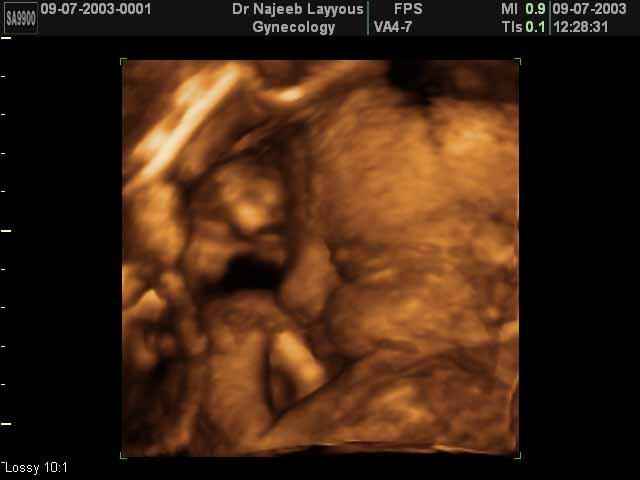

- صور جانبية لرأس الجنين

صور جانبية لرأس الجنين بجهاز الالتراساوند ثلاثي الأبعاد | الدكتور نجيب ليوس